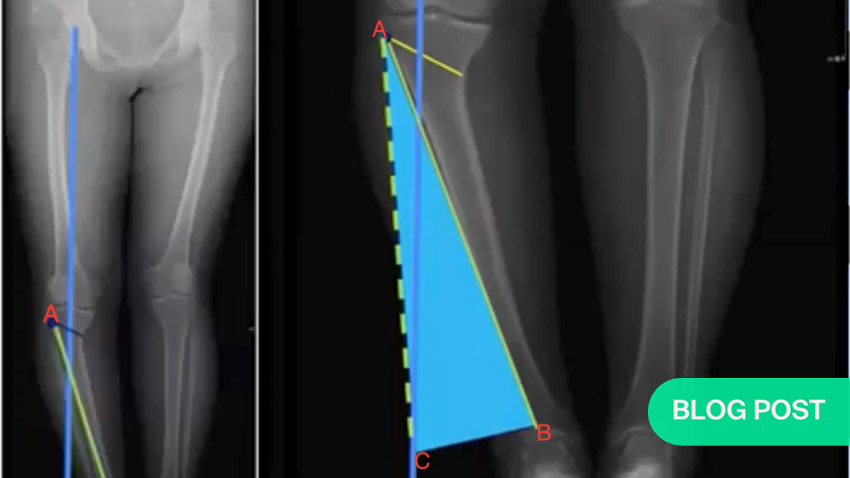

5. Determining the height of the wedge opening (Miniaci method)

The steps to determine the height of the opening necessary for a medial open wedge osteotomy are listed below.

Once you have decided on the location of your hinge point, you can use the Miniaci method to determine the correction angle.

The Miniaci method of determining the correction angle

- Draw a target mechanical axis line directly vertically from the center of the femoral head to level of the foot.

- Draw a second line (line AB) connecting the hinge point (A) to the center of the ankle (B).

- Keeping the origin of line AB on the hinge point, inscribe an arc from the center of the ankle to where it crosses the mechanical axis. That is point C. Join A to C. You now have two lines—AB and AC—of identical length.

- The angle between the two lines from the hinge point (to the current and target position of the ankle) is the alpha angle.

- If there is a self-correction to the joint line convergence angle (JLCA), subtract that from the alpha angle.

- Transfer this angle to the correction site and use a Hernigou trigonometric chart to match the correction angle (alpha minus the JLCA self-correction) to the cut length to locate an opening size.